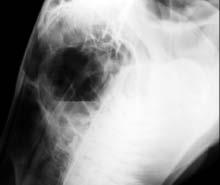

Penn’s George D.Widener Hospital for Large Animals at New Bolton Center became the first hospital (human or animal) in the United States to use a portable digital radiography system with a 14"x17" digital sensor panel. The new equipment,installed in September, enables radiologists to radiograph skulls,necks, and thoracic and abdominal areas ofhorses and other large animals.The previously installed 9"x11" sensor panel permits digital radiographs oflimbs or other small areas.

“This new digital sensor panel allows us to capture a large radiographic image in seconds,” says Dr. Alexia McKnight, lecturer in Radiology at New Bolton Center.“Ifthe image isn’t positioned correctly,we can quickly repeat it.With film we had to wait for the developed image,which took time and often meant that the animal had to be re-sedated if a view needed to be repeated.”

Dr.McKnight explains that digital radiography provides more detailed images than traditional films. Contrast is improved and

information is easier to interpret.This is because the software allows manipulating the raw data to bring into view more diagnostic information.“We can see subtle bony lesions much more clearly on digital radiographs,”says Dr.McKnight.“Also,subtle fractures are visible. They don’t show up on film,and we used to use xerography,which required a significantly higher exposure. The digital system is much more efficient for us and better for the patients because we can perform our study much faster and with shorter sedation time.The ability to accurately measure angles and distances on the

images has also been a wonderful bonus ofthe digital system.It also enhances our referral capabilities because ofthe amount ofdetail we can capture through this technology.”

Conventional radiograph.Digital radiograph.